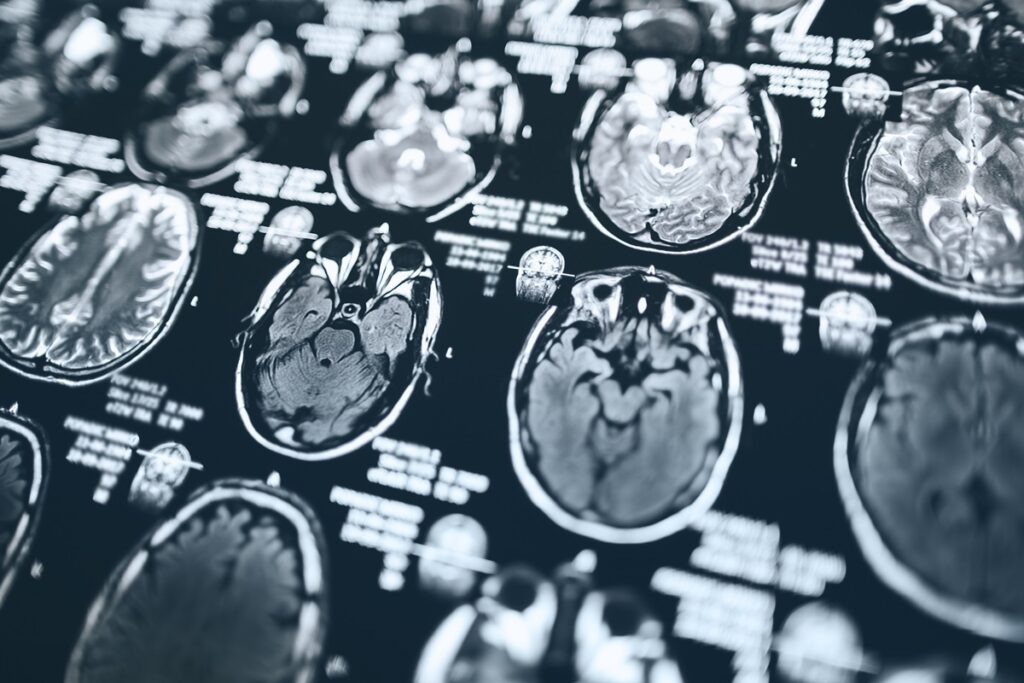

O acidente vascular cerebral, também conhecido como AVC ou derrame cerebral, é a interrupção do fluxo de sangue para alguma região do cérebro

O acidente pode ocorrer por diversos motivos, como acúmulos de placas de gordura ou formação de um coágulo – que dão origem ao AVC isquêmico –, sangramento por pressão alta e até ruptura de um aneurisma – causando o AVC hemorrágico